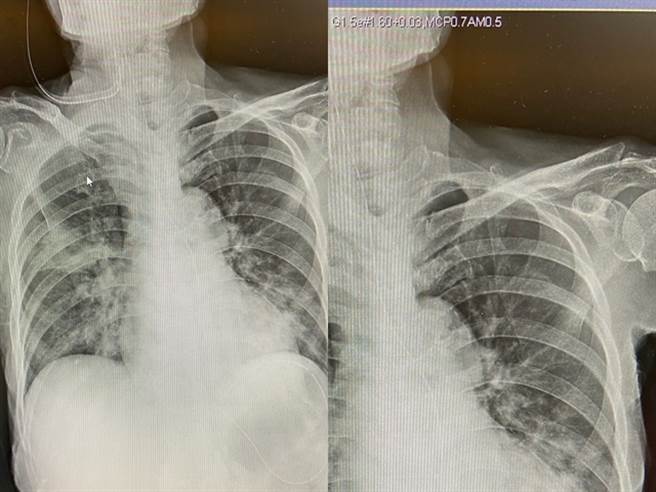

男大生日戴保險套與學姊發生關係,當晚竟「全身重傷」,他PO出X光照片,稱自己頭皮撕裂傷、右手斷掉,最後曝光原因,原來他是被「學姊男友」打傷。(翻攝自Dcard)

還有網友說「忍耐一分鐘,提早領年終」要原PO向學姊男友索賠,其他人則說「可以色色又有錢」,也有人質疑原PO的X光照片是假的,因為心臟異常肥大、有放鼻胃管,且醫院通常不會讓病人拍電腦影像,懷疑是醫學系學生盜拍病患的圖,痛罵非常可恥。